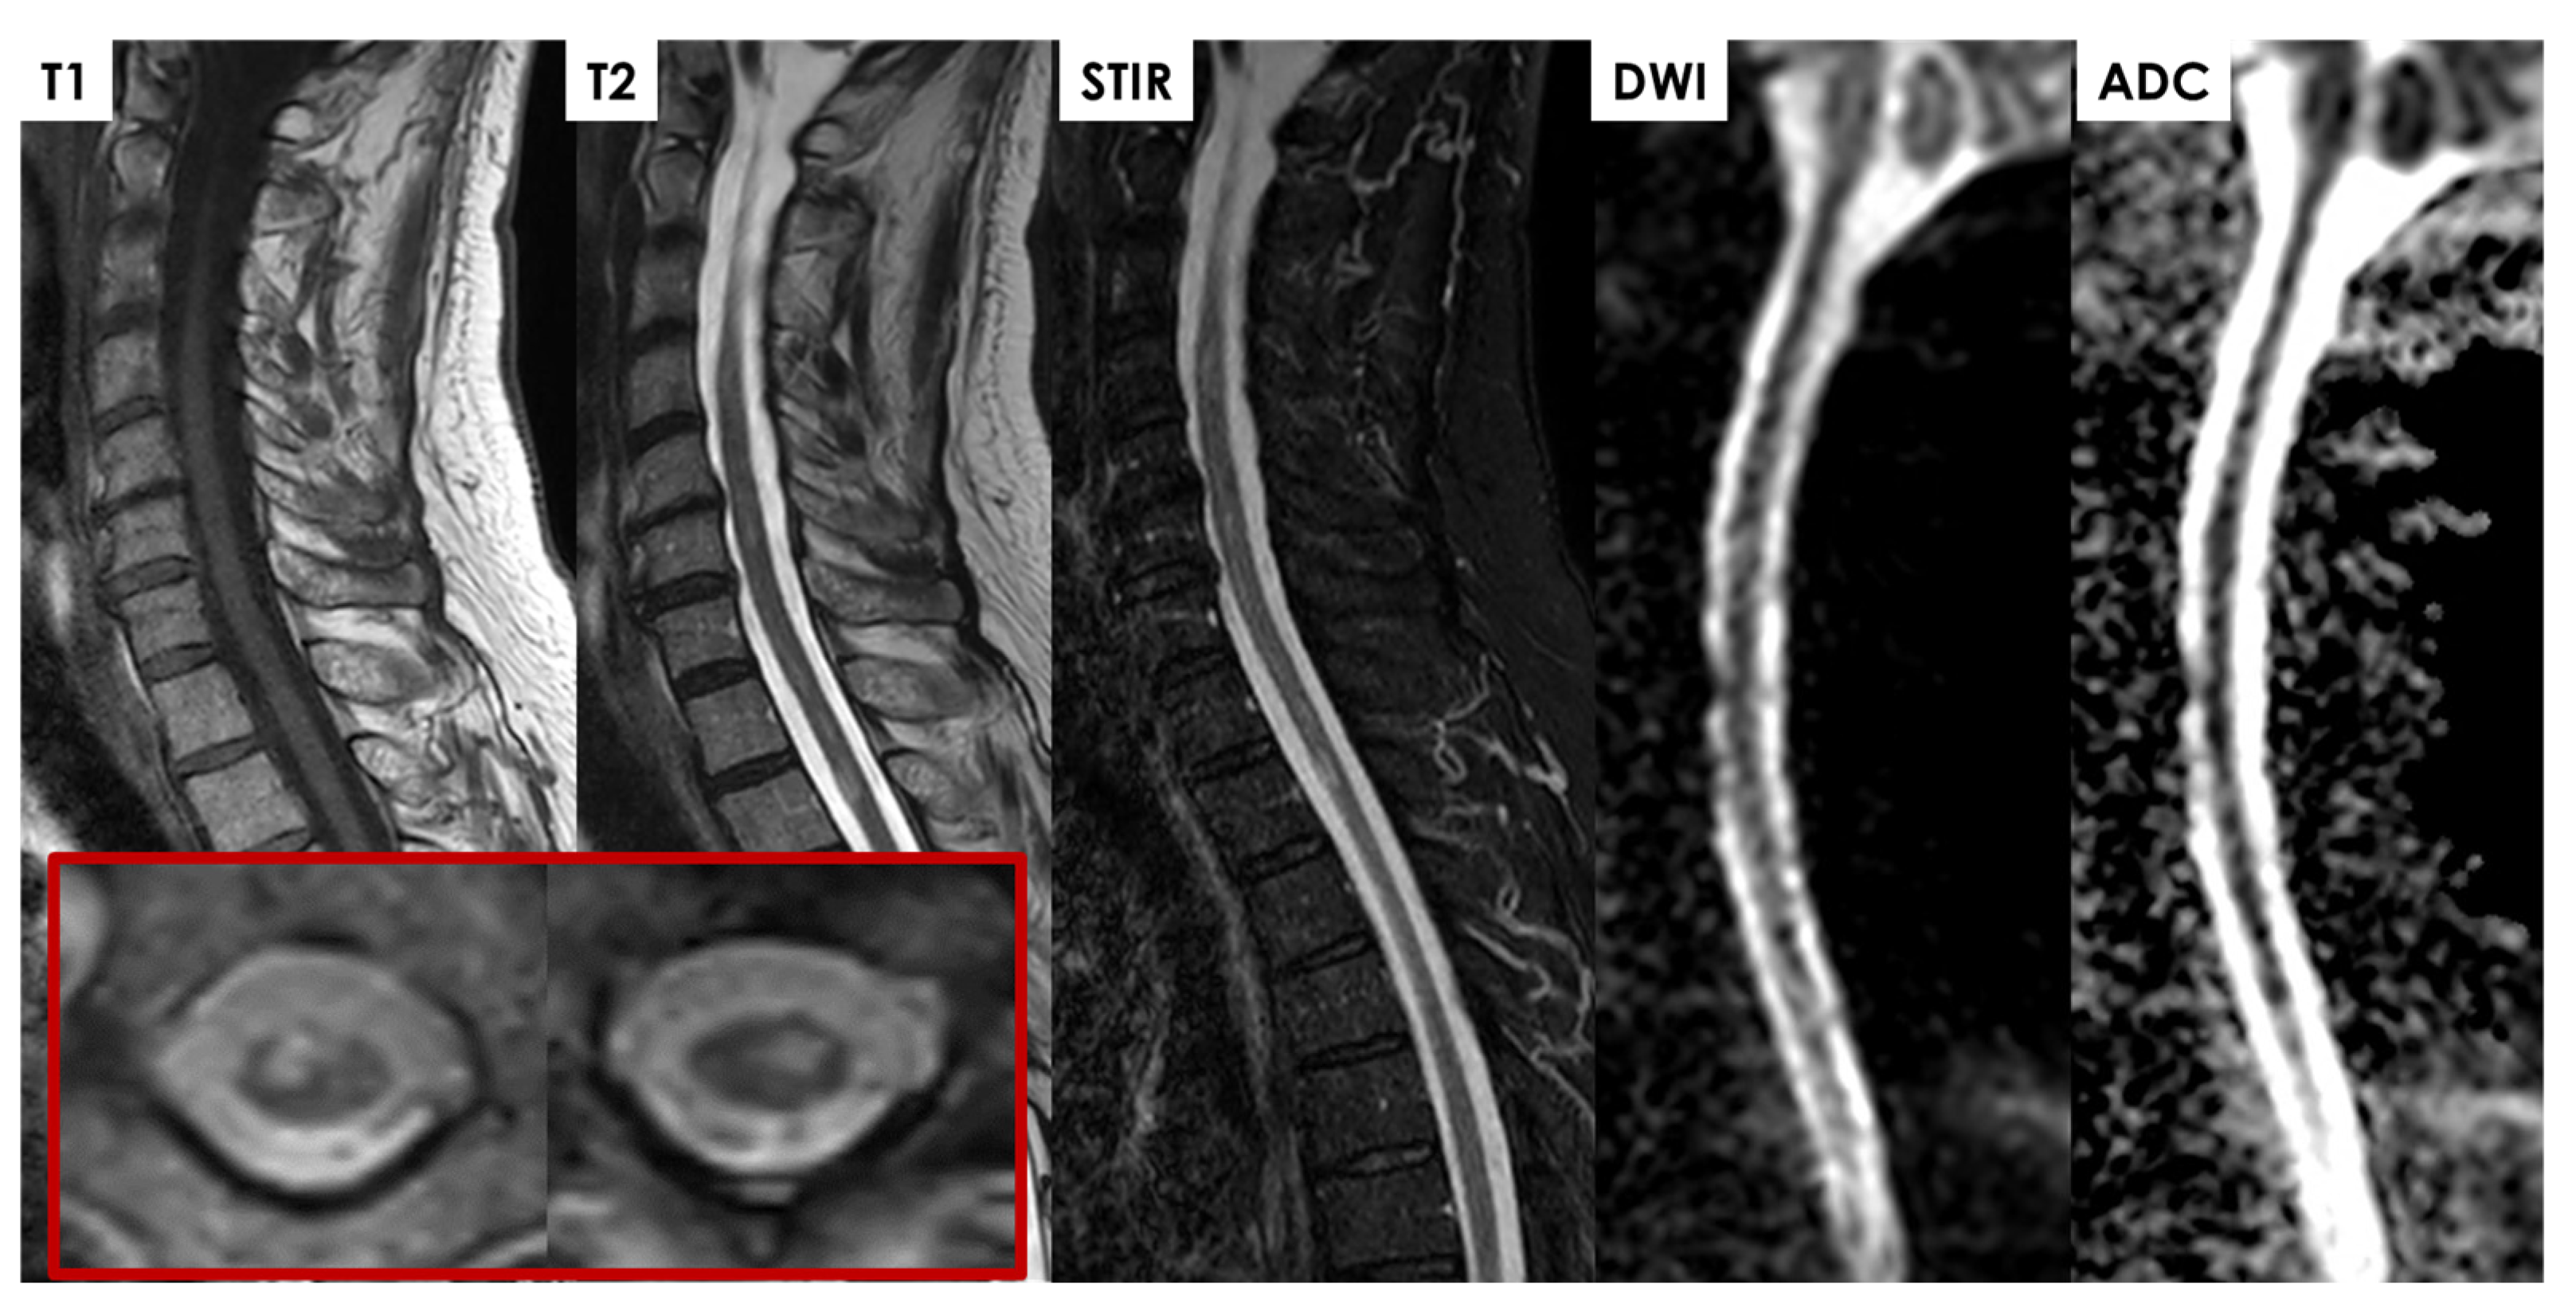

- Restricted diffusion, with a high signal on DWI and low signal on apparent diffusion coefficient (ADC) images, is similar to arterial infarcts in the brain;

- ASA infarcts on T2-weighted images commonly show central gray matter involvement, with an H- or butterfly-shaped appearance, or the “owl’s eyes” or “snake-eyes” sign;

- In the hyperacute and acute phases, parenchymal T2-hyperintensity appears non-expansile, thin, and pencil-like on sagittal images;